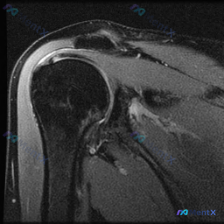

髋关节MRI读片分享:大转子周围软组织高信号的分析思路 拿到这张髋关节冠状位T2序列MRI,先整理一下影像基本信息: 影像基本情况 扫描范围覆盖右侧髋关节,包含股骨头、股骨颈、股骨近端、髋臼及部分盆腔结构,解剖结构清晰,股骨头形态正常,髋臼包绕股骨头形态正常。 关键影像发现 1. 骨骼与关节内结构:...